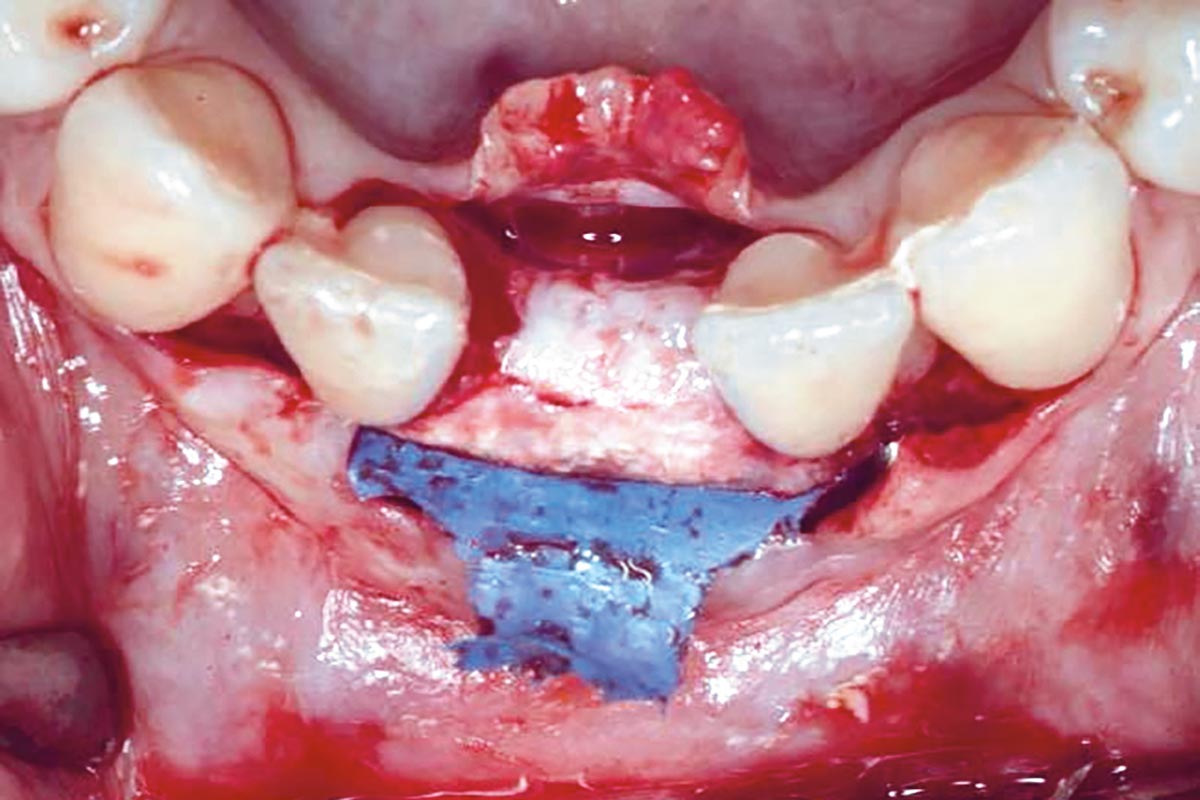

Regenerative corticotomy to compensate lower incisor malocclusion with cerabone® and mucoderm®

Initial view of the clinical case: Class III malocclusion

Treatment plan: Regenerative corticotomy (PAOO)